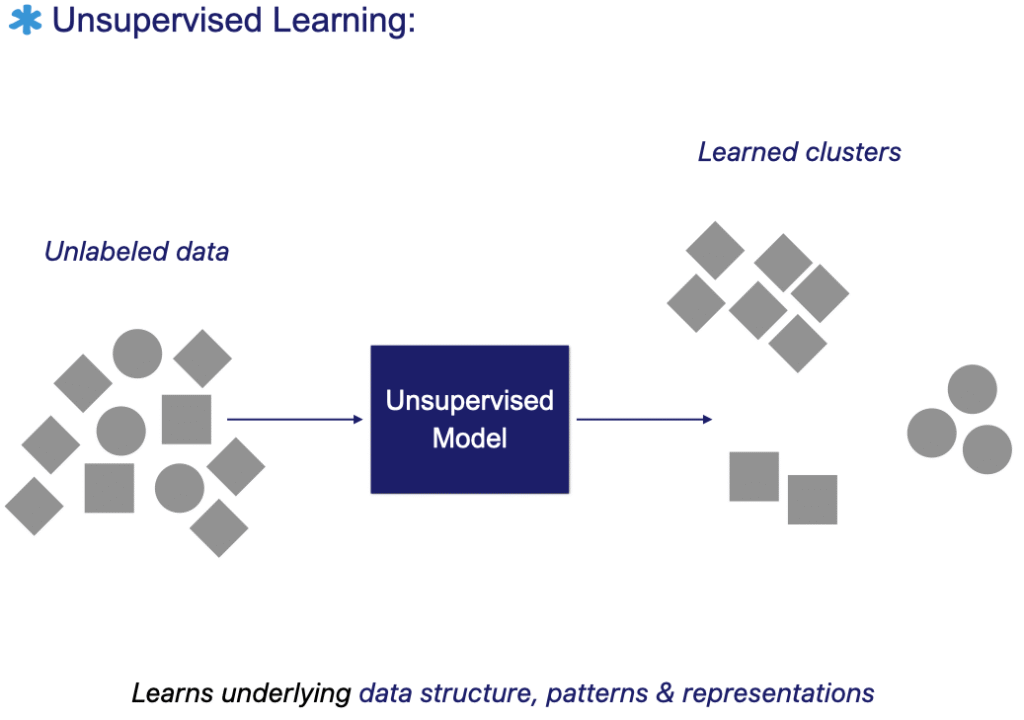

Unsupervised machine learning algorithms extract patterns and structure directly from raw data, without relying on predefined labels. The model learns to understand the underlying distribution of the data and can therefore group or cluster similar images.

Beyond clustering, unsupervised methods can learn compressed and meaningful representations that support data-driven decision-making. Their strength lies in their generality. These models often serve as a foundation for a wide range of downstream tasks.

Unsupervised learning is not limited to classification. It is also used for dimensionality reduction, compression, denoising, super-resolution, and even certain forms of autonomous decision-making. In practice, it is often advantageous to learn such representations before knowing the exact task they will serve.

The representations learned through unsupervised methods can later enhance the generalization and performance of supervised models trained on limited labeled data [6, 7], as will be further illustrated in self-supervised learning.

The figure below illustrates the unsupervised learning workflow: the model is trained directly on unlabeled data to discover patterns, clusters, or meaningful representations without predefined labels.